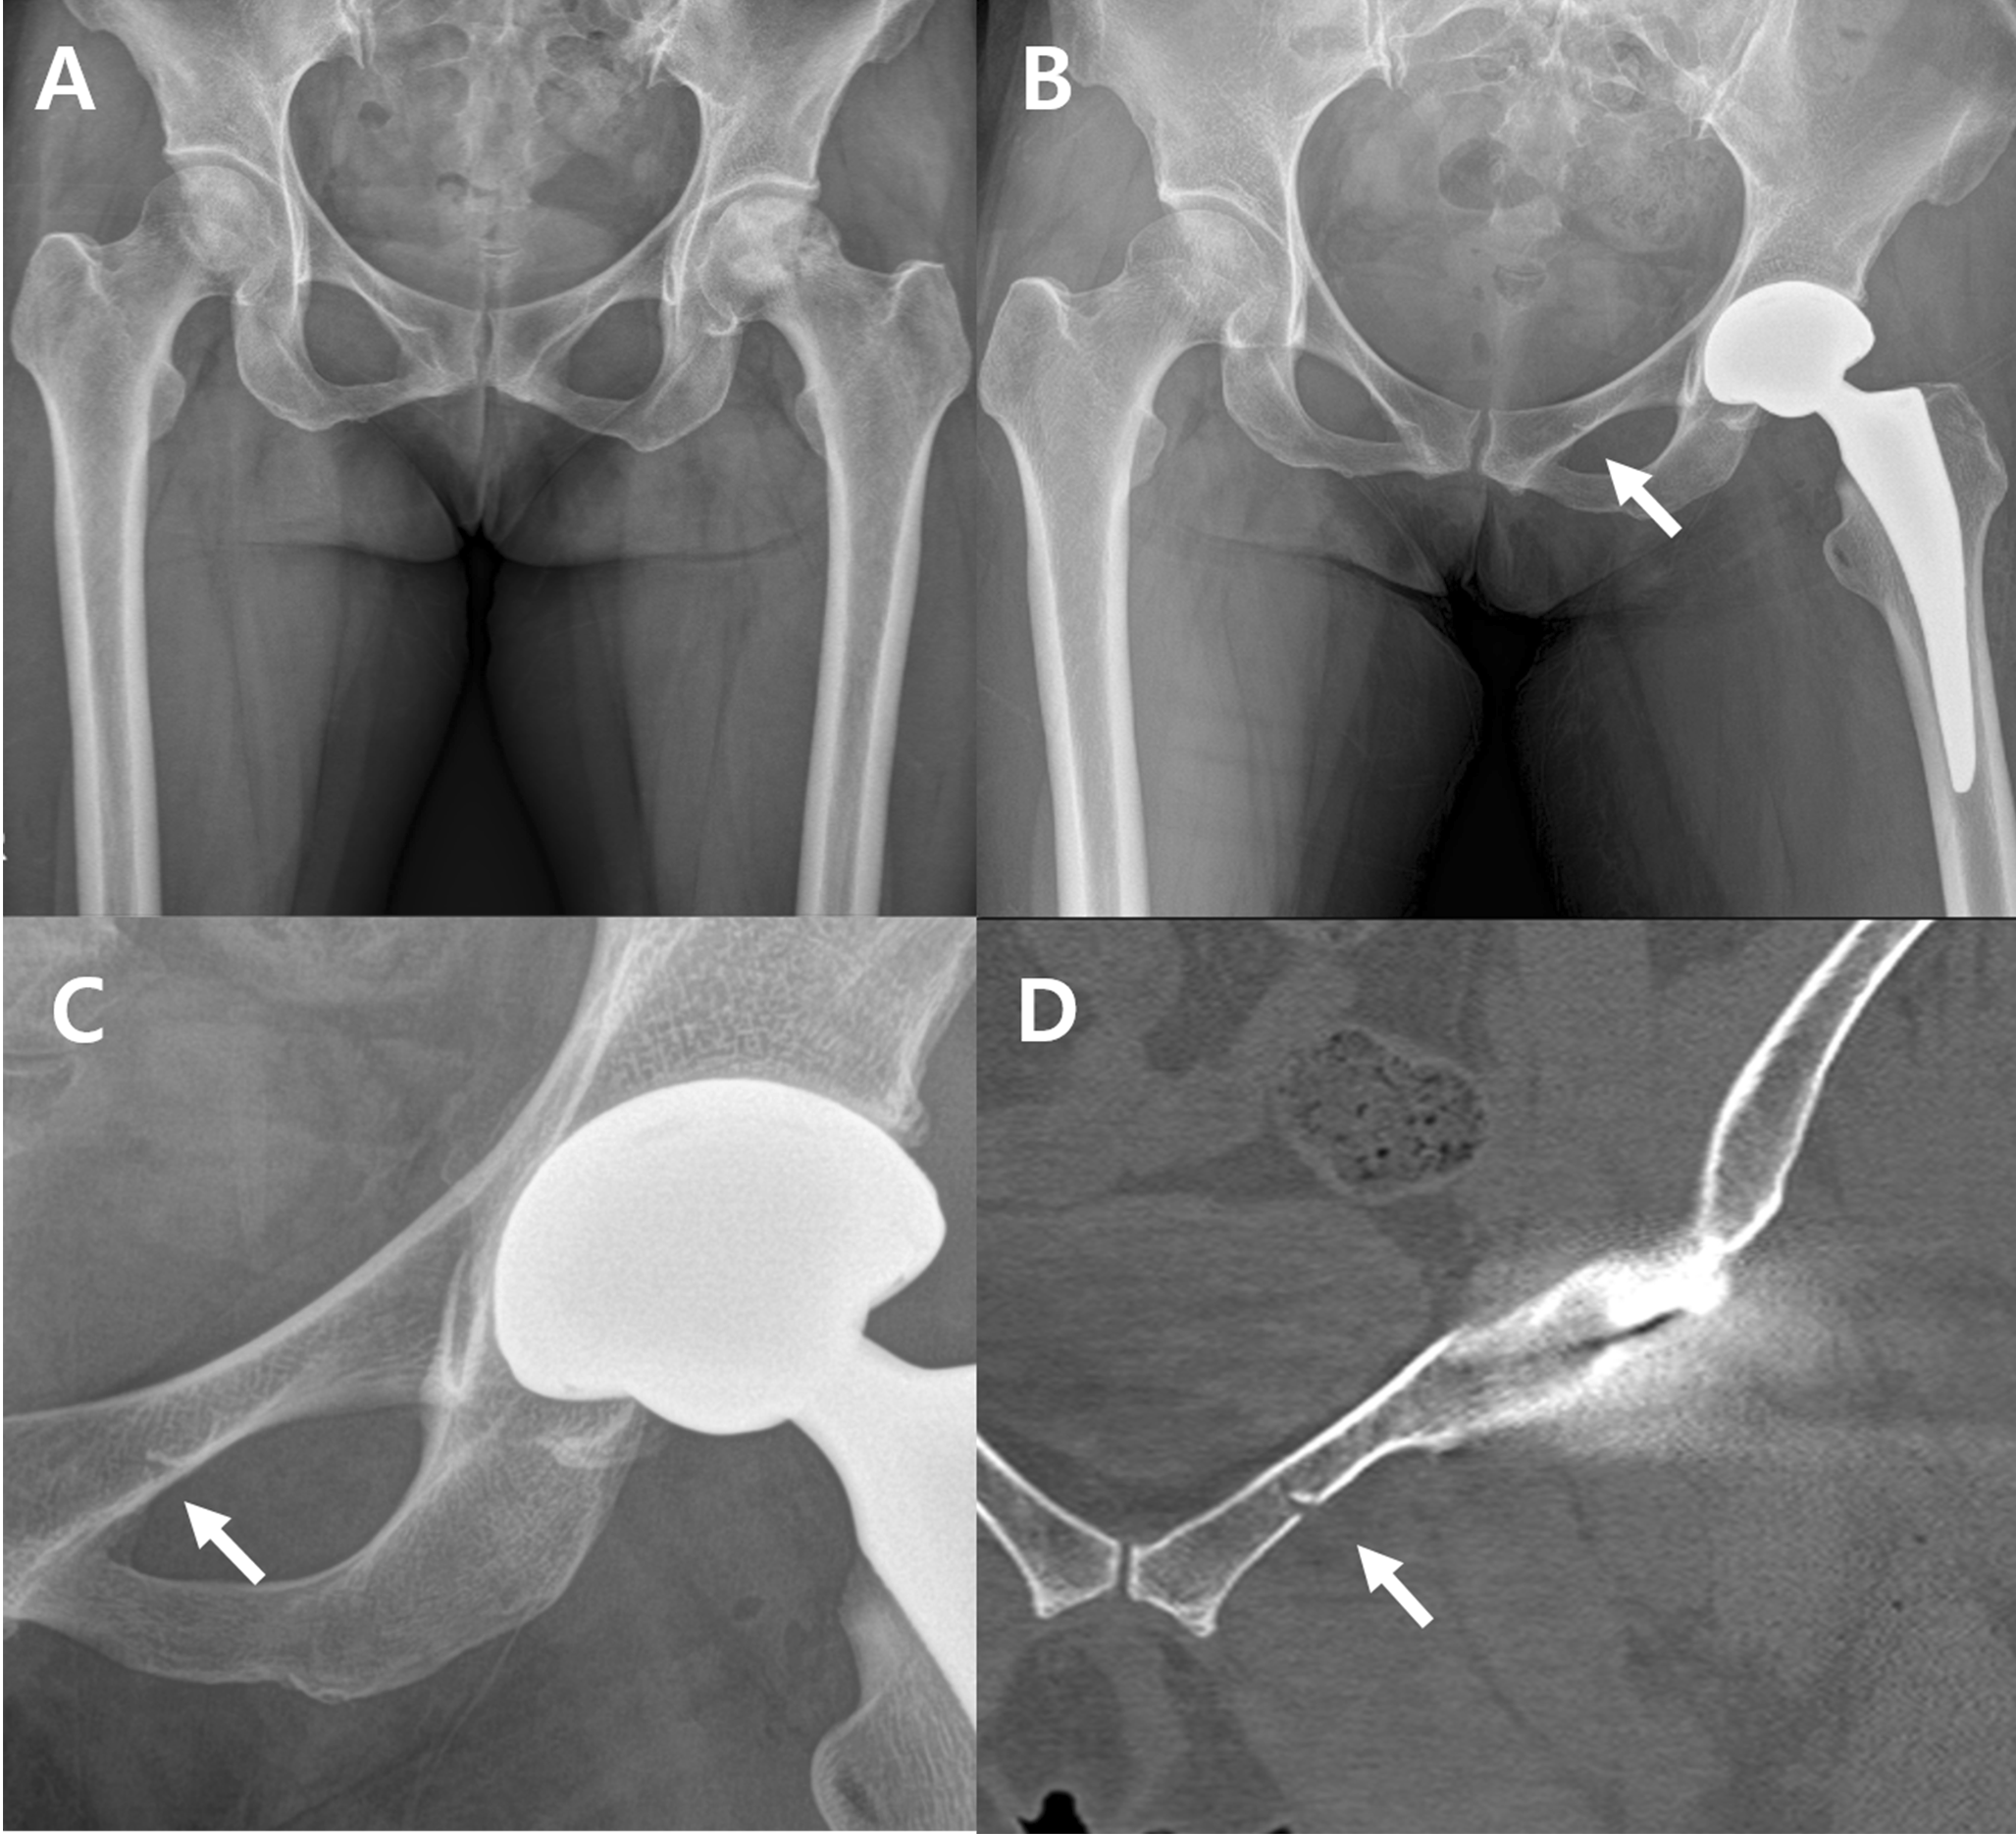

Fig. 4

Radiographs showing an inferior pubic ramus fracture during total hip arthroplasty. (A) Preoperative anteroposterior view. (B) Fragmented fractures (arrow) on the right inferior pubic ramus are visible on the postoperative hip anteroposterior radiograph. (C) Magnified view. (D) The postoperative hip computed tomography axial view reveals comminuted fractures on the right inferior pubic ramus

Occult fractures were most frequently found in the superior pubic ramus, accounting for 10 out of 22 hips (45.4%) (Figs. 2 and 3). Fractures of the inferior pubic ramus were observed in 9 hips (40.9%) (Fig. 4), while 1 hip (4.5%) exhibited fractures in both pubic rami. Fractures involving the peri-acetabulum were observed in 2 hips (9.0%), with one hip showing an extension of the fracture into the superior pubic ramus and the other hip showing extension of the fracture into the inferior pubic ramus. No fractures were observed in the pubic symphyseal area (Table 1).